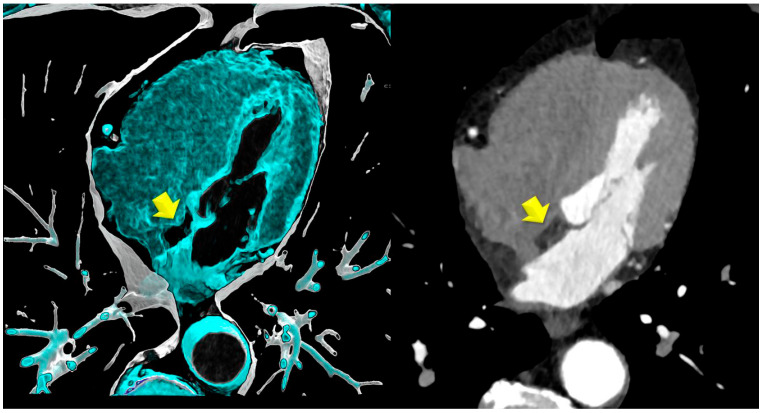

背景:虽然心外膜脂肪组织(EAT)是已知的不良心血管结局的预测因子,但心房间隔脂肪瘤性肥厚(LHIS)是由代谢活性脂肪(如棕色脂肪组织)组成的,它可能发挥不同的作用。本研究使用CTA研究LHIS患者的冠状动脉粥样硬化概况,并与倾向评分匹配的对照组进行比较。方法:共纳入142例患者(LHIS组71例,对照组71例),对年龄、性别、BMI和主要CV危险因素(匹配水平)进行倾向评分匹配。结果:平均年龄60.9岁+/- 10.6岁,女性9例(6.3%),平均BMI为28.04 kg/m2 +/- 4.99。LHIS患者HRP患病率明显低于对照组(21.1%比40.8%,p < 0.011),而CAC (p = 0.827)和CADRADS (p = 0.329)差异无统计学意义,在阻塞性疾病发生率上无统计学差异。脂质组(胆固醇、低密度脂蛋白、高密度脂蛋白、甘油三酯)和他汀类药物摄取率没有差异。结论:LHIS患者HRP患病率低于对照组,冠状动脉狭窄严重程度和CAC评分差异无统计学意义。临床相关性:LHIS可作为逆转CV风险的成像生物标志物。

Background: While epicardial adipose tissue (EAT) is a known predictor of adverse cardiovascular outcomes, lipomatous hypertrophy of the interatrial septum (LHIS) is composed of metabolically active fat such as brown adipose tissue, which may exert a different effect. This study investigates the coronary atherosclerosis profile in patients with LHIS using CTA, compared with a propensity score-matched control group. Methods: A total of 142 patients were included (n = 71 with LHIS and n = 71 controls) and propensity score-matched for age, gender, BMI, and the major CV risk factors (matching level, <0.05). CTA imaging parameters included HRP, coronary stenosis severity (CADRADS), and CAC score. Results: The mean age was 60.9 years +/- 10.6, there were nine (6.3%) women, and the mean BMI is 28.04 kg/m2 +/- 4.99. HRP prevalence was significantly lower in LHIS patients vs. controls (21.1% vs. 40.8%; p < 0.011), while CAC (p = 0.827) and CADRADS (p = 0.329) were not different, and there was no difference in the obstructive disease rate. There was no difference in lipid panels (cholesterol, LDL, HDL, TG) and statin intake rate. Conclusions: HRP prevalence is lower in patients with LHIS than controls, while coronary stenosis severity and CAC score are not different. Clinical relevance: LHIS may serve as imaging biomarker for reversed CV risk.